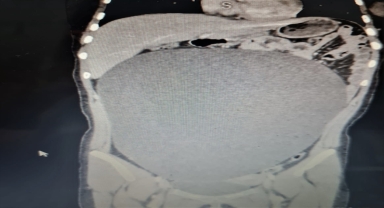

Genç kız, "kazayla" karnındaki dev kitleden kurtuldu